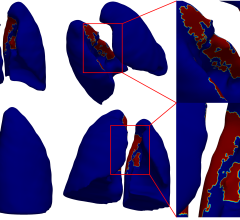

Body Vision CEO Dorian Averbuch said the product targets small pulmonary nodules that, if diagnosed early, can be resected to cure lung cancer. The technology provides step-by-step guidance through planning, navigation and lesion localization during biopsy.

"Body Vision provides a great tool that has changed the way we approached peripheral nodules. Its unique technology creates augmented reality with the ability to see fluoroscopically invisible lesions and the pathways under the live fluoro, while tracking a patient breathing," said D. Kyle Hogarth, M.D., FCCP, president of the Society for Advanced Bronchoscopy, associate professor of medicine, director of bronchoscopy at the University of Chicago. "Once the technology has guided us to the lesion, we confirm the lesion's relationship to the airway with radial-EBUS [endobronchial ultrasound]. We then use our off-the-shelf biopsy instruments via the LungVision catheter. The augmented fluoro image, integrated with the radial EBUS images, allows us to obtain tissue samples with continuous real-time confirmation of location. The beauty of it all is how simple and elegant the technology is."